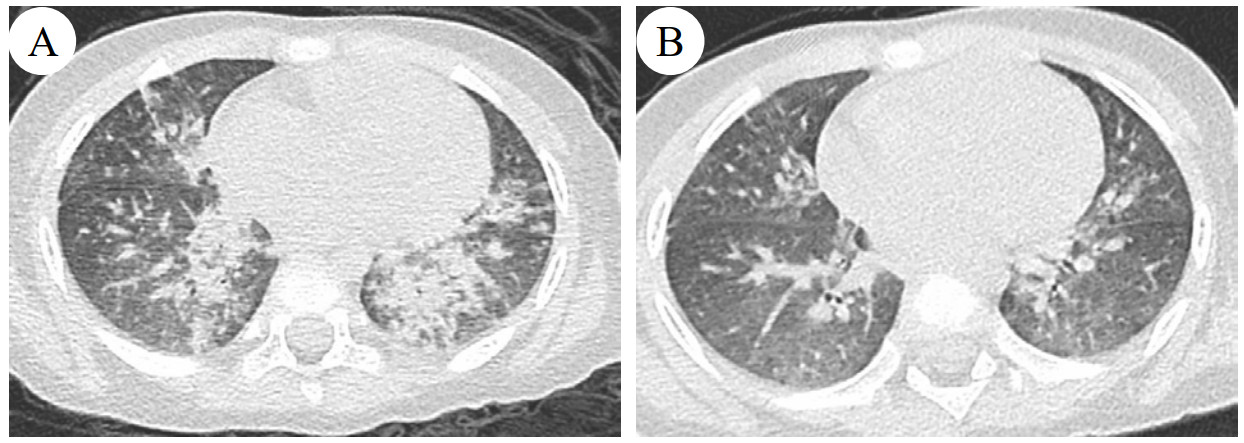

查体:体重13 kg,体温36.9 ℃,心率160次/min,呼吸频率45次/min,血压103/62 mmHg(1 mmHg=0.133 kPa),经皮血氧饱和度95%;镇静状态,双侧瞳孔等大等圆,直径3 mm,对光反应稍迟钝;呼吸急促,伴有喉中发声,双肺呼吸音粗,可闻及粗湿啰音;心律齐,心音有力,腹软,肝脾肋下未及双巴氏征阳性。辅助检查:血常规示白细胞3.86×109/L,红细胞4.62×1012/L,血红蛋白113 g/L,中性粒细胞比率52.8%,淋巴细胞比率41.2%,血小板225×109/L,C-反应蛋白52.1 mg/L,降钙素原13.72 ng/mL,胆碱酯酶5 739 U/L。血气分析示酸碱度7.26,二氧化碳分压46.3 mmHg,氧分压89.6 mmHg,乳酸1.6 mmol/L,碳酸氢根19.2 mmol/L,碱剩余6.4 mmol/L;血生化示:丙氨酸氨基转移酶18.7 U/L,天门冬氨酸氨基转移酶60.7 U/L,肌酐27.2 µmol/L,肌酸激酶165 U/L,肌酸激酶同工酶5.17 ng/mL,肌钙蛋白T 0.052 ng/mL,N端-B型钠尿肽前体149.2 pg/mL,神经元特异性烯醇化酶33.36 ng/mL,白介素-6 153.5 pg/mL,血钙2.03 mmol/L,血钾3.79 mmol/L,血钠136.5 mmol/L,血糖6.85 mmol/L。床边胸片示双肺纹理增多模糊、可见斑片状影(图 1);心电图、心脏彩超未见异常;脑脊液常规检测未见异常。血液、尿液标本行毒物筛查结果显示血液中四氟苯菊酯浓度为20 ng/mL,尿中监测到四氟苯菊酯;视频脑电图示背景活动异常,双侧后头部为主3-5Hz中-高波幅混合慢波活动,夹杂多量低波幅快波,左右大致对称。

| 图 1 患者入院当天床边胸片 |